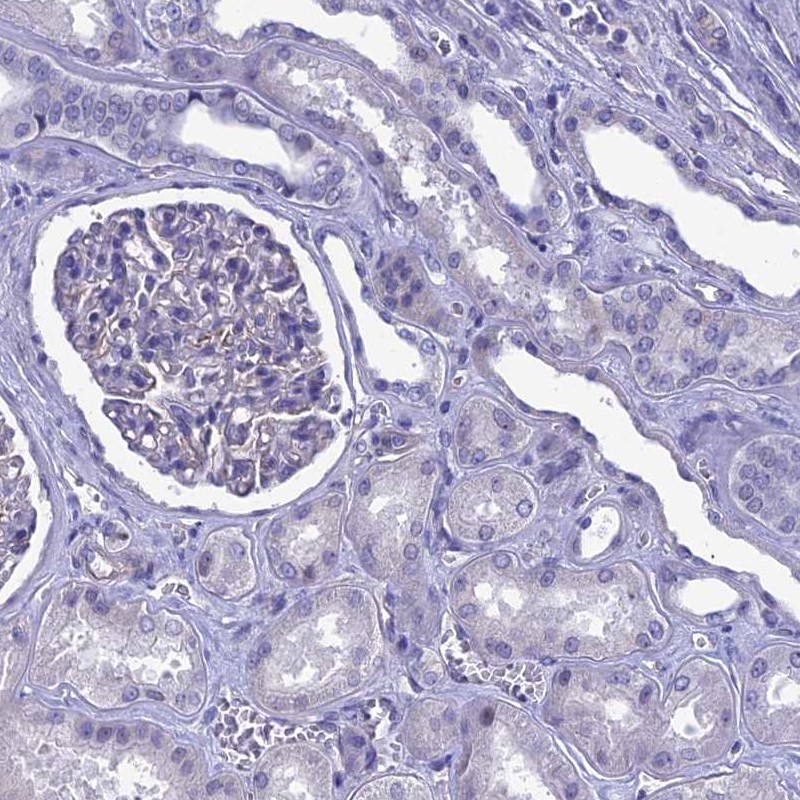

Immunohistochemistry analysis in human cerebral cortex and kidney tissues using Anti-SLC1A6 antibody. Corresponding SLC1A6 RNA-seq data are presented for the same tissues.